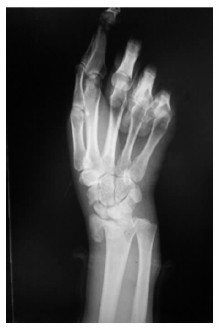

1.2 治疗方法急诊予以常规患侧腕关节正侧位X线片,必要时CT三维重建(图 1、2)。均采用臂丛麻醉,仰卧位,常规消毒铺巾,止血带止血。开放者直视下克氏针穿针固定,闭合骨折由助手牵引,手法复位纠正侧方移位,成角及短缩畸形,术中X线透视,骨折块或关节面复位不满意可借助克氏针撬拨复位或有限切开复位,复位满意后用多枚克氏针交叉固定。克氏针以刚穿出骨皮质为宜,以增加牢度,克氏针尾部折弯留于皮外,骨折初步复位后予以安装动力型外固定架,选择超关节外固定架,先于第二掌骨背外侧作2个0.5 cm切口,间距以外固定架钉夹为准,平行植入2枚2.5 mm支架螺钉,在距桡骨骨折线4~6 cm桡骨上置入2枚支架螺钉,安装并调整外固定架,保证远端球形活动关节位于桡腕关节水平线上,利于早期功能锻炼,同时调整外固定架施以适当牵引力,保持腕关节轻度尺偏掌曲位并锁紧,直至透视满意。术后第2天开始手指伸屈曲能锻炼,术后第1天,4周,6周、8周及3个月复查X线片(图 3、4),4周松外固定架锁紧装置开始功能锻炼,4~6周拔除克氏针,6~8周拆除外固定架。

| 图 1 急诊正位片 |